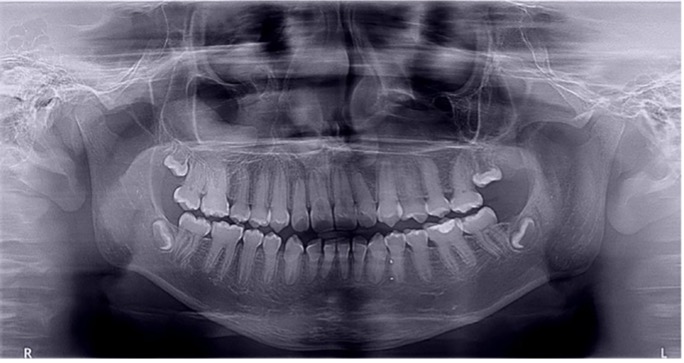

El examen clínico intraoral reveló alteración de la estructura y color de las piezas primarias, atrición y pérdida de la dimensión vertical (Figura 2). Radiográficamente se observó la presencia de coronas con marcada constricción cervical y raíces cortas (Figura 3). Presentaba alto riesgo cariogénico, por la presencia de lesiones de caries activas y dos restos radiculares, sumado a la anomalía estructural de la dentina (riesgo biológico específico) y bajo riesgo gingivoperiodontal. El riesgo socio-económico era alto por provenir de una familia con marcadas limitaciones económicas. Luego de la anamnesis, examen clínico y radiográfico, e interconsulta con el médico de cabecera se estableció el diagnóstico de DI Tipo I asociado a OI tipo I. Se planificó un tratamiento integral y preventivo con los objetivos de devolver forma y función, y proteger y evitar el desgaste de los tejidos conductas que pudieran interferir con el tratamiento.

Figura 3: Radiografía panorámica año 2007

En la radiografía panorámica de control del año 2015 se observó la progresiva obliteración del conducto radicular en el grupo incisivo superior e inferior y en los primeros molares permanentes; presentado los premolares en erupción, un conducto radicular anormalmente amplio en toda su longitud (Figura 8). En la del año 2018 se visualizó la continua aposición de dentina a nivel radicular que obliteró en forma casi total los conductos de la mayoría de las piezas dentarias, a excepción de los segundos molares inferiores (Figura 10).

Debido el alto porcentaje de abscesos periapicales, producto de la obliteración progresiva de los conductos radiculares, es fundamental el monitoreo radiográfico periódico en pacientes con DI.1 Los controles con radiografías panorámicas fueron realizados en el 2007, 2010, 2015 y 2018, sin registro de patologías pulpares periapicales.